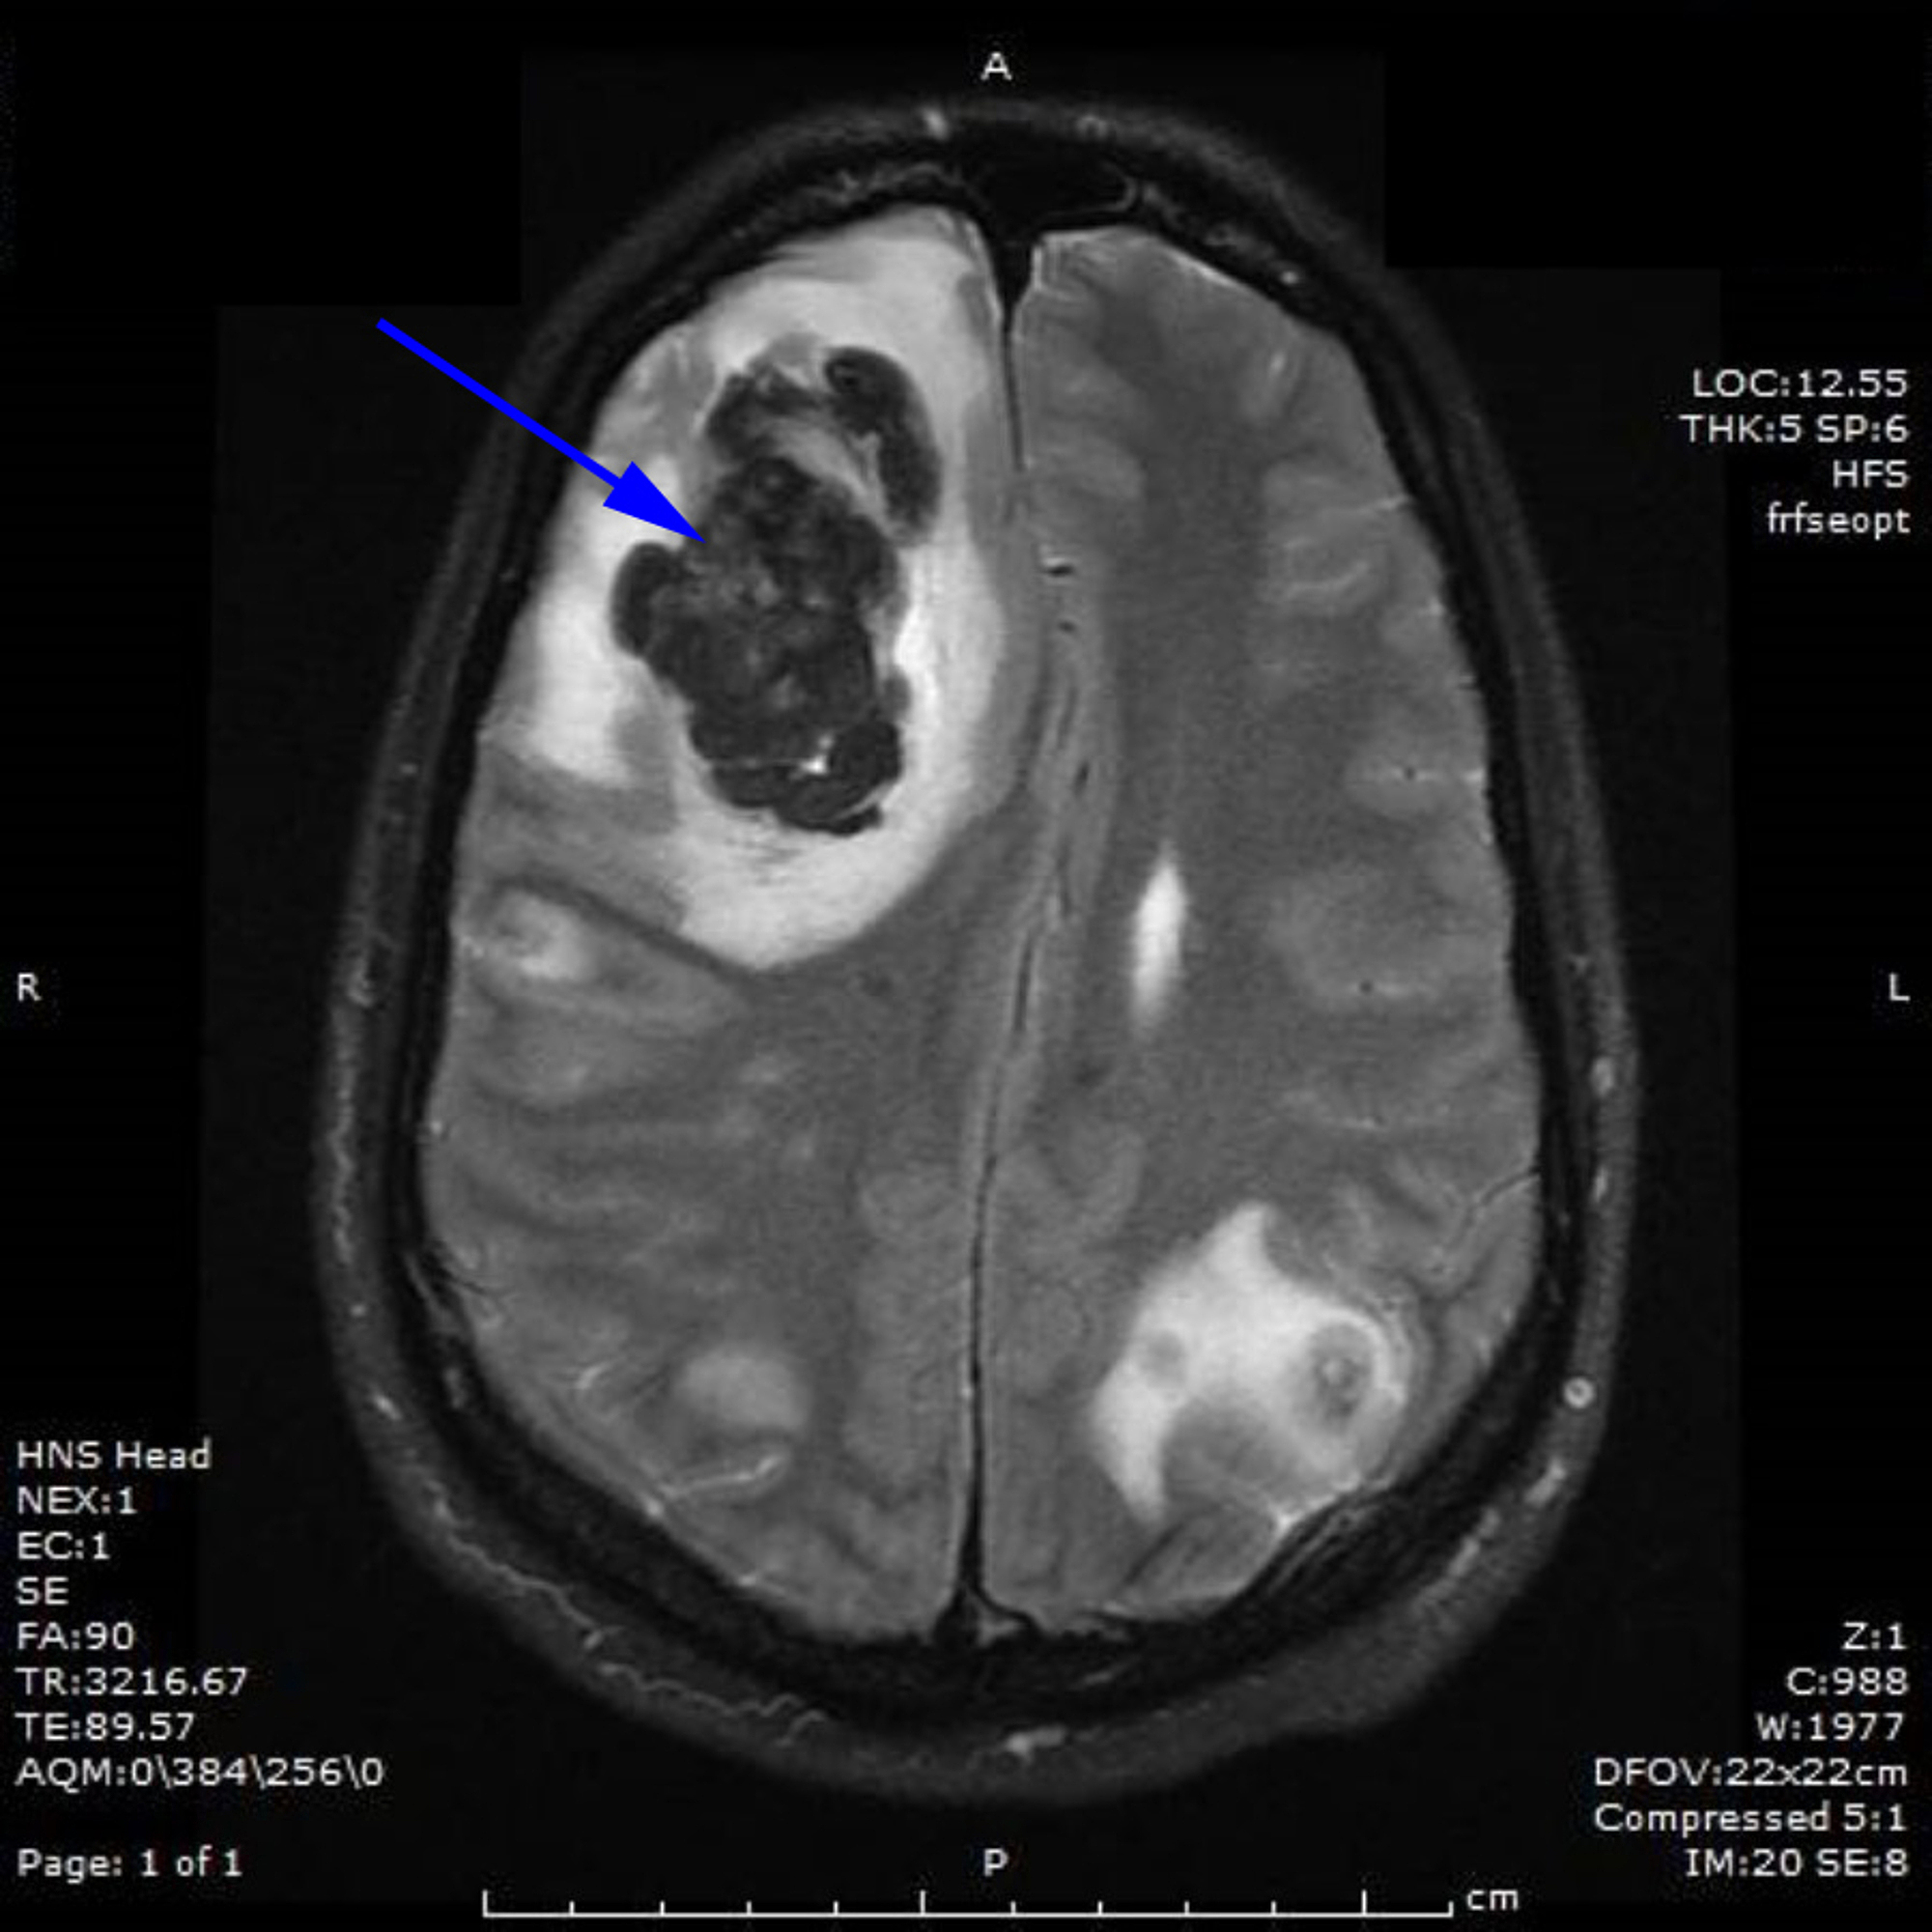

Cerebral metastases testicular choriocarcinoma Image Testicular Cancer Brain Metastases Symptoms Signs and symptoms caused by brain metastases can vary based on the location, size and rate of growth of the metastatic. Our study evaluated the incidence, imaging characteristics, and prognosis of brain metastases originating. 1 most cases with brain. testicular cancer with neurological symptoms indicates brain metastases. A feeling of heaviness in. A lump or swelling in either testicle;. Testicular Cancer Brain Metastases Symptoms.

Cureus Pure Testicular Choriocarcinoma with Dermatological, Brain Testicular Cancer Brain Metastases Symptoms Our study evaluated the incidence, imaging characteristics, and prognosis of brain metastases originating. Signs and symptoms caused by brain metastases can vary based on the location, size and rate of growth of the metastatic. 1 most cases with brain. signs and symptoms of testicular cancer include: A feeling of heaviness in. testicular cancer with neurological symptoms indicates brain. Testicular Cancer Brain Metastases Symptoms.